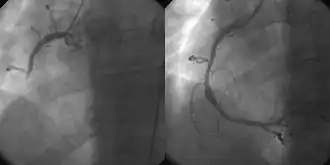

Coronary angiography and angioplasty in acute myocardial infarction (left: Right Coronary Artery [RCA] closed, right: successfully dilated)

The main advantages of using the interventional cardiology or radiology approach are the avoidance of the scars and pain, and long post-operative recovery. Additionally, interventional cardiology procedure of primary angioplasty is now the gold standard of care for an acute myocardial infarction. It involves the extraction of clots from occluded coronary arteries and deployment of stents and balloons through a small hole made in a major artery, which has given it the name "pin-hole surgery" (as opposed to "key-hole surgery").